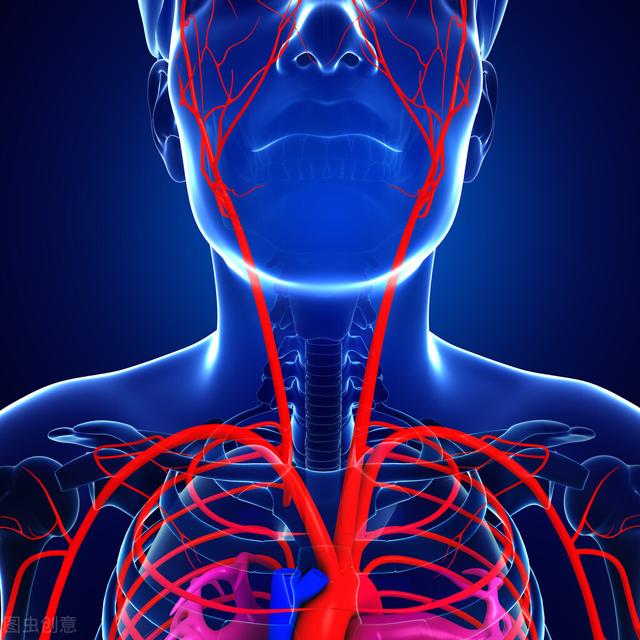

Voyons d'abord quels sont les vaisseaux sanguins qui mènent au cerveau. Comme nous pouvons le voir sur l'image fournie, les vaisseaux sanguins qui mènent au cerveau sont l'artère carotide et l'artère vertébrale, ce qui signifie que ces deux vaisseaux sanguins assurent l'approvisionnement en sang du cerveau, l'artère carotide assurant les 2/3 de l'approvisionnement en sang et l'artère vertébrale assurant le 1/3 de l'approvisionnement en sang. Si l'artère carotide est bloquée, l'irrigation sanguine des 2/3 du cerveau est affectée et le cerveau présente une série de symptômes de manque d'oxygène.

Tout d'abord, examinons les deux systèmes vasculaires qui alimentent notre cerveau : l'artère carotide interne et l'artère vertébrale.

Les artères carotides internes, l'une à gauche et l'autre à droite, sont situées à l'avant de notre cou et nous pouvons les toucher et les sentir pulser. Elles alimentent en sang les deux premiers tiers du cerveau.

Les artères vertébrales se trouvent à l'intérieur de notre colonne cervicale, également une à gauche et une à droite, et assurent principalement l'approvisionnement en sang du tiers arrière de notre cerveau et du cervelet.